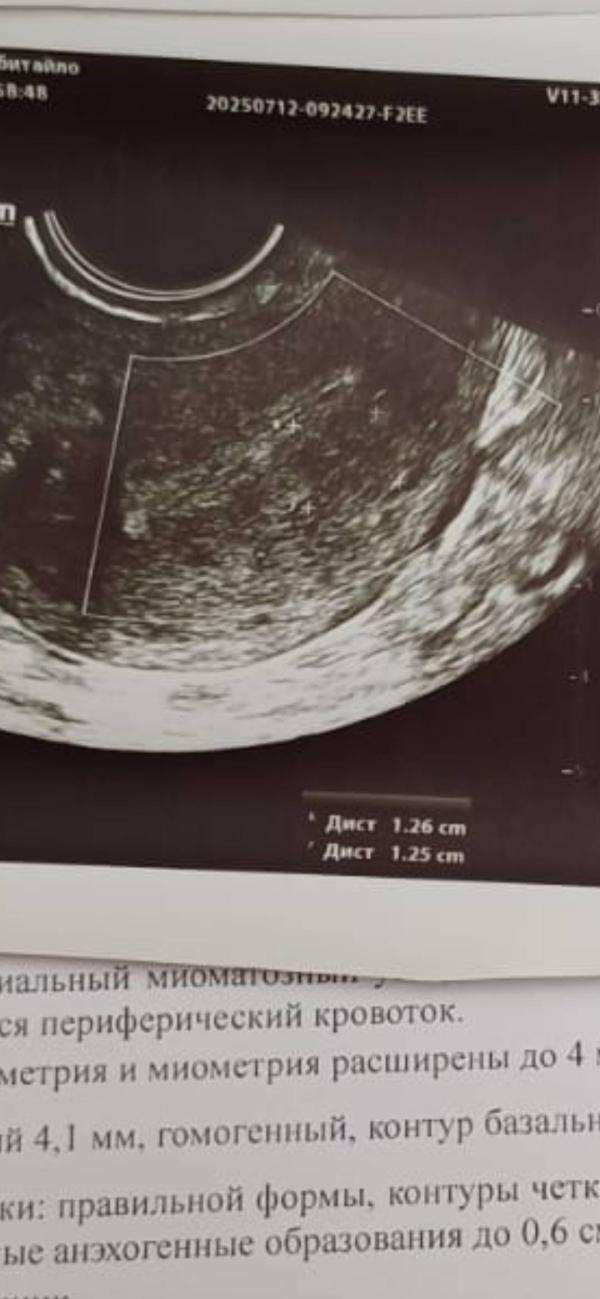

Делала узи орагнов малого таза перед гистероскопией . Октябрь 2023. Узел . Размеры указаны и тд

Минутку... 3 разных узи и везде узел. Деформирующий эндометрией

Вот такие горе врачи в перенатальном центре. Даже фото есть этого узла...а оперирующий ничего не видет.